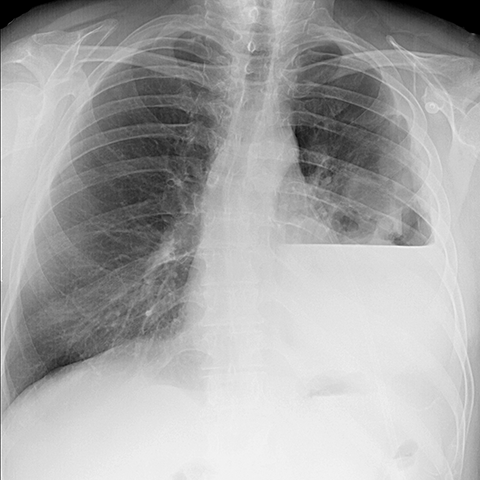

Left Empyema (PA CXR) [1 of 2]